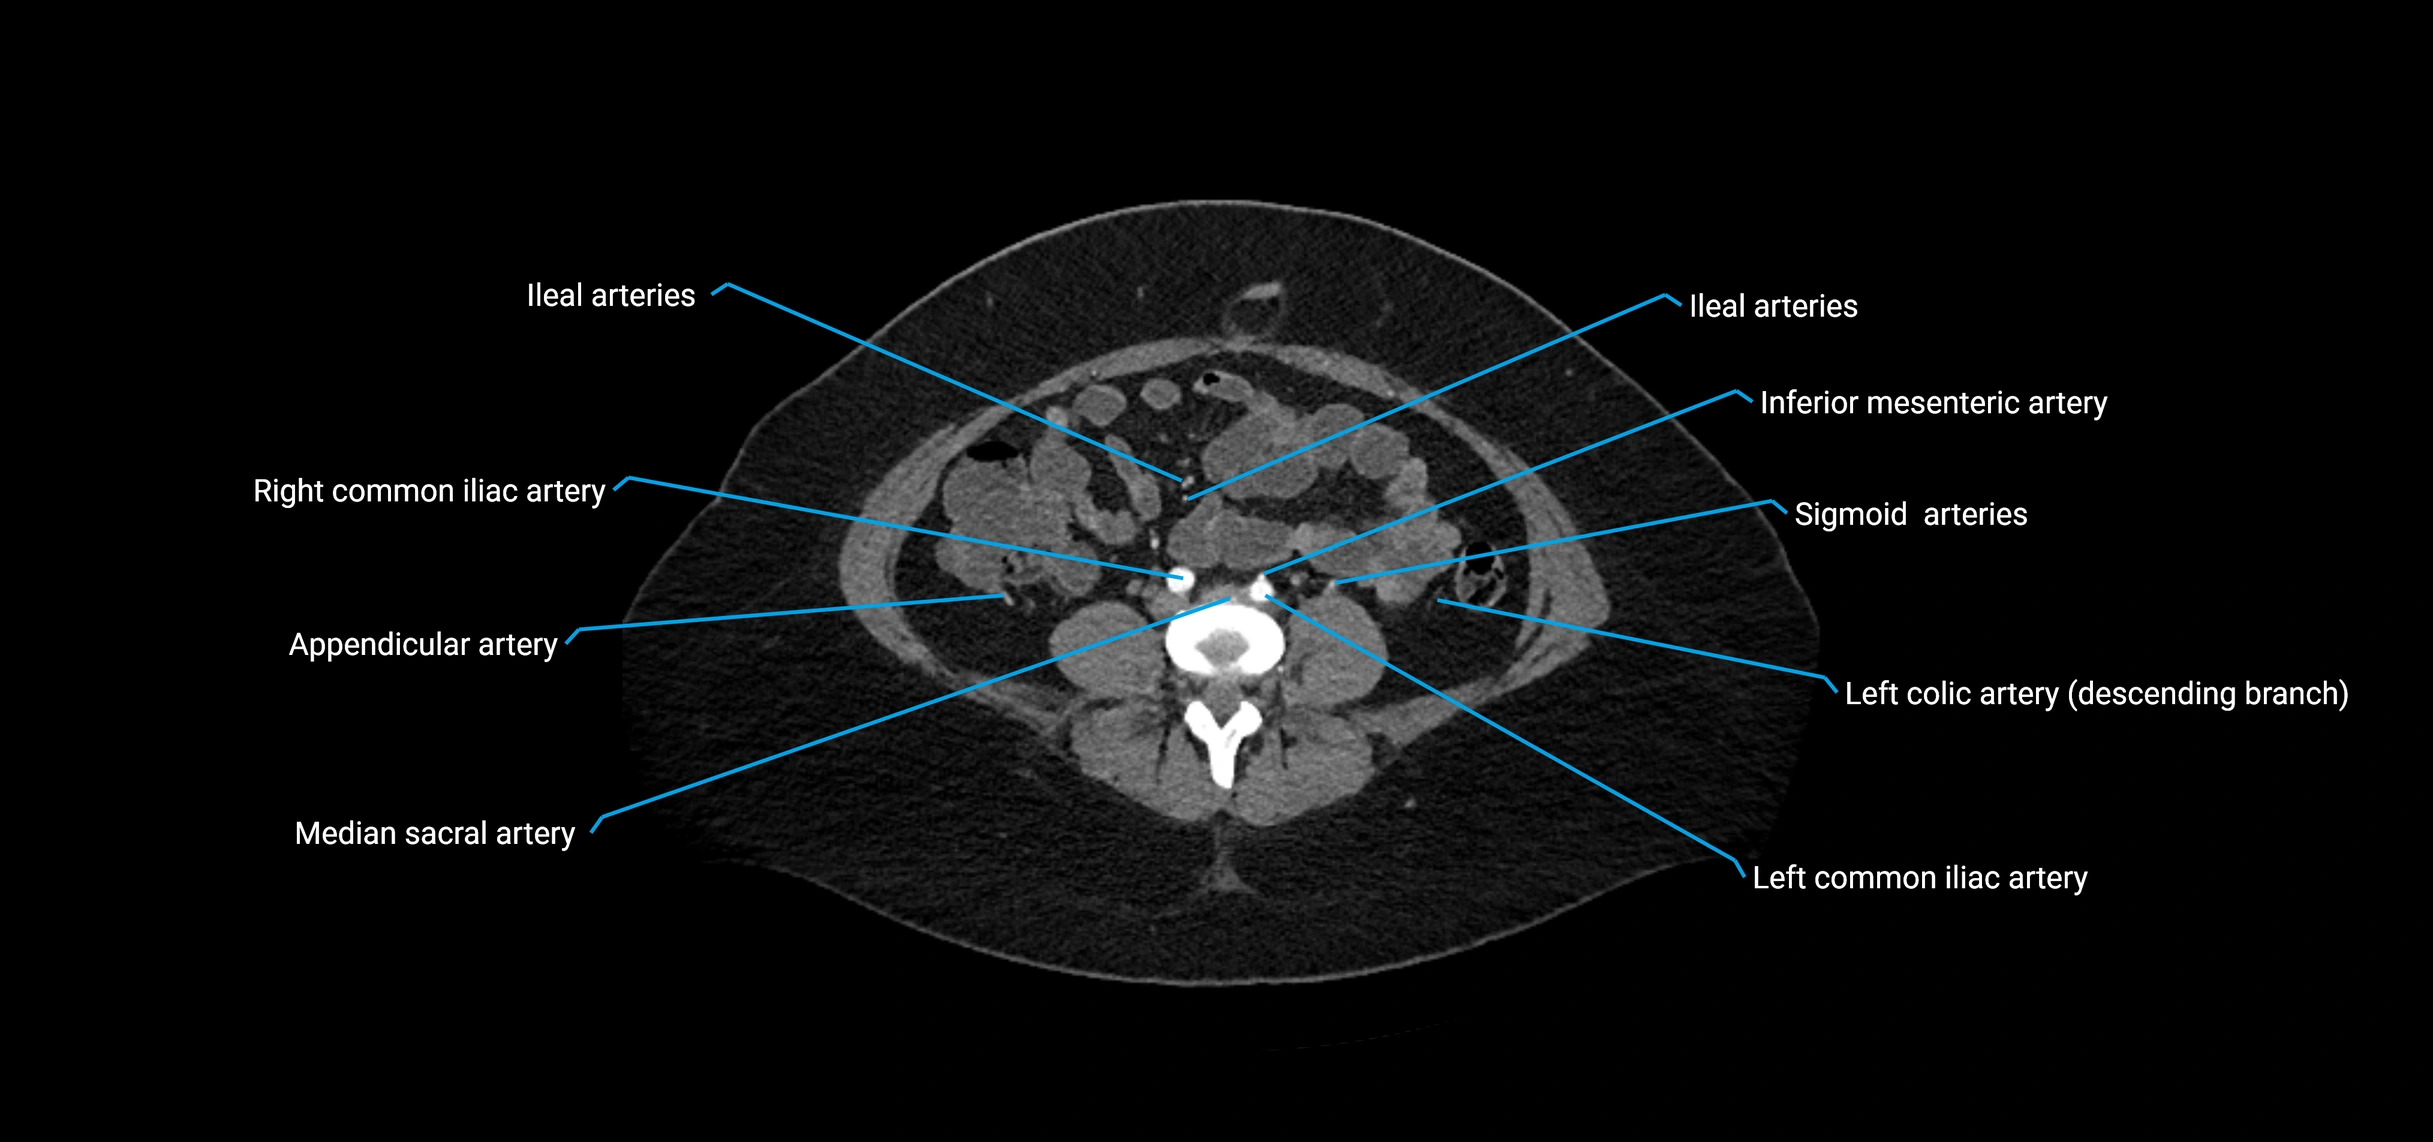

Contrast-enhanced CT (CTA):

• Gold standard for abdominal aortic imaging

• Provides excellent detail of lumen, wall, aneurysm, thrombus, and branch vessels

• Multiplanar and 3D reconstructions help in aneurysm measurement, stent graft planning, and dissection evaluation

• Detects acute rupture, traumatic injury, or occlusion with high sensitivity